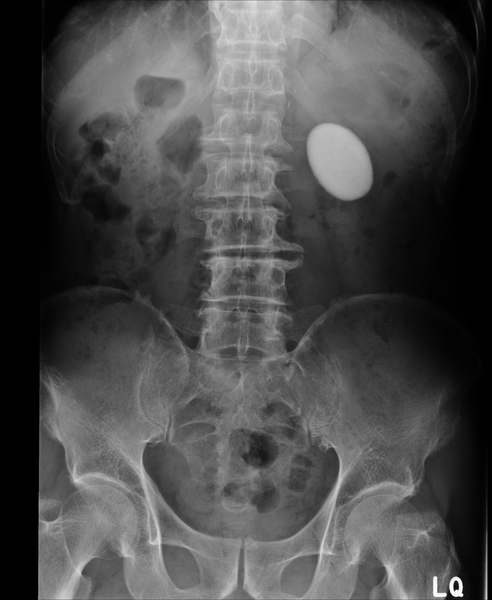

這張圖裡可見到兩側腎臟有嚴重的結石。